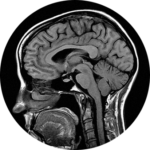

Magnetic Resonance Imaging: MRI

How does it work?

How did we get from the image on the left to the one on the right?

The great progenitor of MRI is NMR (nuclear magnetic resonance). The phenomenon of magnetic resonance was initially discovered by physicists, after which chemists turned the basic science into NMR, an essential tool for probing the structure and dynamics of molecules. In a classic story of how science works, physicists, chemists, and physicians are all responsible for the initial and continuing development of MRI, and the story of these connections provides a classic glimpse of how science works and of the occasional controversies associated with Nobel Prizes.

This presentation describes the path from molecular beams studied in vacuum to probe fundamental properties of matter all the way to the widespread use of non-invasive MRI to diagnose an impressive range of medical conditions. In addition, on the research front we’ll look at the use of MRI to pursue the tantalizing question of ‘what is thought.’ Along the way we’ll also talk about why the scanner makes a banging noise that many who have experienced liken to a jackhammer.